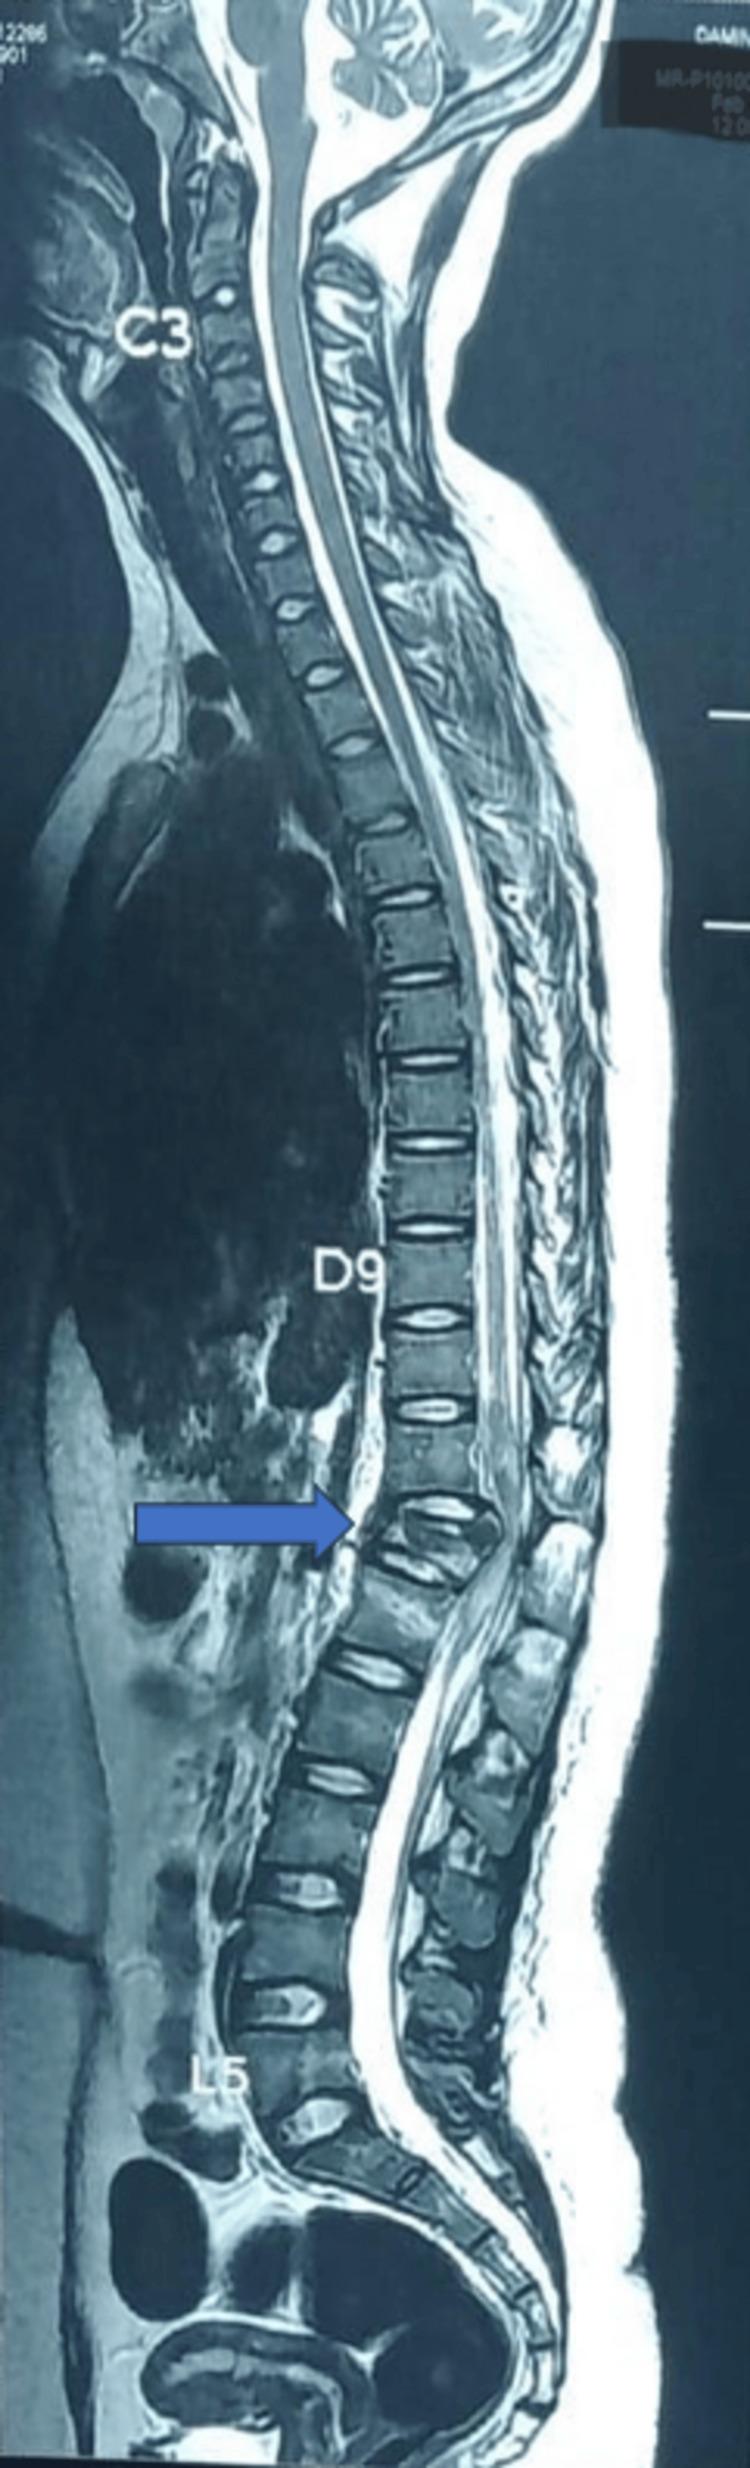

Spinal anesthesia (SA) has emerged as a viable alternative to general anesthesia (GA) for thoracolumbar spine surgeries. The double-needle technique (DNT) aims to enhance the precision and efficacy of SA in these procedures. The DNT (SA at two levels) involves performing two separate spinal punctures at different vertebral interspaces during the same procedure, often used to optimize anesthesia spread. This case series evaluates the feasibility, safety, and clinical outcomes of DNT in patients undergoing thoracolumbar spine fracture fixation. This case series includes five patients diagnosed with thoracolumbar spine fractures who underwent surgical fixation under SA using the DNT. Data on patient demographics, intraoperative hemodynamics, sensory and motor blockade characteristics, anesthesia-related complications, and postoperative recovery were collected and analyzed. All patients achieved adequate surgical anesthesia with the DNT. Hemodynamic stability was maintained in most cases, with minimal vasopressor requirements. None of the patients required conversion to GA. Multimodal analgesia was used to manage postoperative pain. No major anesthesia-related complications were observed. The DNT appears to be a safe and effective approach for SA in thoracolumbar spine surgery. It offers hemodynamic stability, adequate surgical anesthesia, and prolonged postoperative analgesia. Further studies with larger sample sizes are warranted to validate these findings.

对于胸腰椎手术,脊髓麻醉(SA)已成为全身麻醉(GA)的一种可行替代方案。双针技术(DNT)旨在提高SA在这些手术中的精准度和效果。DNT(在两个节段进行SA)包括在同一手术过程中于不同椎间隙进行两次单独的脊髓穿刺,常用于优化麻醉平面扩散。本病例系列评估了DNT在接受胸腰椎骨折固定手术患者中的可行性、安全性和临床结局。该病例系列包括五例诊断为胸腰椎骨折的患者,他们在SA下采用DNT接受了手术固定。收集并分析了患者人口统计学数据、术中血流动力学、感觉和运动阻滞特征、麻醉相关并发症及术后恢复情况。所有患者通过DNT均获得了足够的手术麻醉。大多数情况下血流动力学保持稳定,血管升压药需求极少。无患者需要转为GA。采用多模式镇痛管理术后疼痛。未观察到重大麻醉相关并发症。DNT似乎是胸腰椎手术中SA的一种安全有效的方法。它提供血流动力学稳定性、足够的手术麻醉和延长的术后镇痛效果。有必要进行更大样本量的进一步研究以验证这些发现。